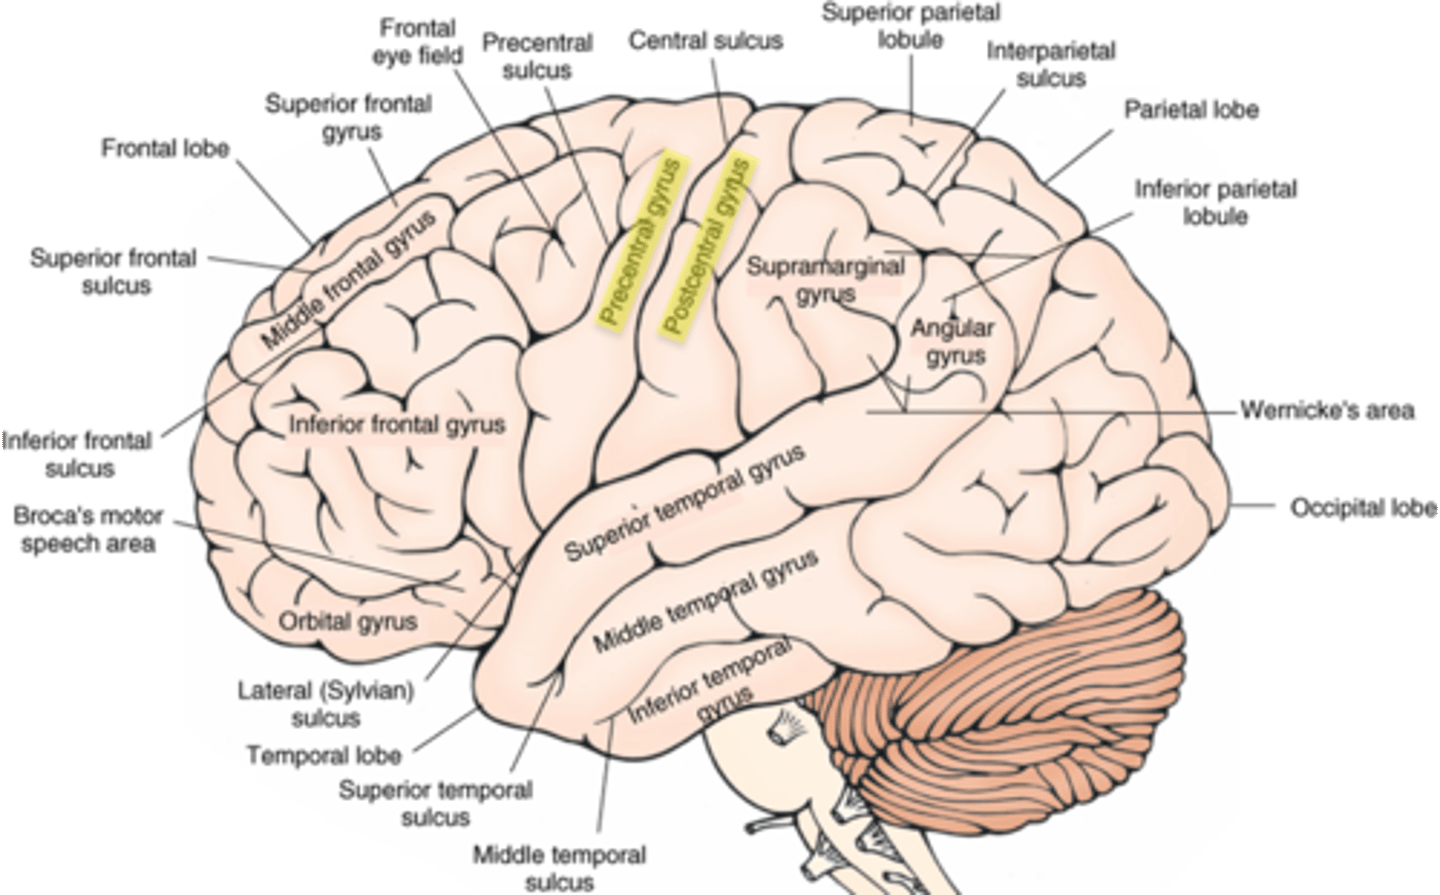

what are the 4 main lobes of the cerebrum?

FPOT

1. frontal

2. parietal

3. temporal

4. occipital

what lobe of the cerebrum is involved with motor and personality?

FPOT

frontal

what lobe of the cerebrum is involved with sensory?

FPOT

parietal

what lobe of the cerebrum is involved in hearing and memory?

FPOT

temporal

what lobe of the cerebrum is involved in vision?

FPOT

occipital

which sulcus separates the cerebral hemispheres?

longitudinal fissure

which sulcus divides the frontal lobe from the parietal lobe and divides the precentral and postcentral gyrus?

central sulcus

which sulcus divides the parietal lobe from the temporal lobe?

lateral (sylvian) sulcus/fissure

which sulcus separates the parietal lobe from the occipital lobe?

parieto-occipital sulcus

which gyrus is the primary motor complex?

precentral gyrus

which gyrus is the primary somatosensory complex?

postcentral gyrus